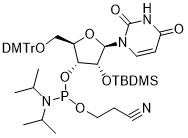

馬鞍山致研生物醫(yī)藥科技有限公司成立于馬鞍山市鄭浦港新區(qū)現(xiàn)代產(chǎn)業(yè)園。公司專(zhuān)注于生物小分子、醫(yī)藥中間體相關(guān)產(chǎn)品的研發(fā)和生產(chǎn),產(chǎn)品主要包括DNA亞磷酰胺單體、RNA亞磷酰胺單體、特殊單體以及按照客戶(hù)要求定制的RNA和DNA,并且公司提供定制合成等方面的研究服...

馬鞍山致研生物醫(yī)藥科技有限公司成立于馬鞍山市鄭浦港新區(qū)現(xiàn)代產(chǎn)業(yè)園。公司專(zhuān)注于生物小分子、醫(yī)藥中間體相關(guān)產(chǎn)品的研發(fā)和生產(chǎn),產(chǎn)品主要包括DNA亞磷酰胺單體、RNA亞磷酰胺單體、特殊單體以及按照客戶(hù)要求定制的RNA和DNA,并且公司提供定制合成等方面的研究服...